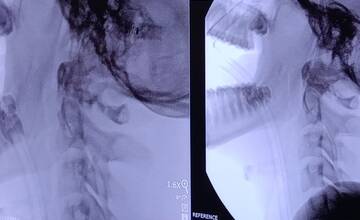

Zlomenina krčného stavca

Na druhú operáciu bol vybraný 15-ročný chlapec, ktorý utrpel zlomeninu druhého krčného stavca pri havárii. „Išlo o zlomeninu zuba čapovca – dens axis. Práve pre túto diagnózu sme vyhodnotili ako vhodnú použiť metódu jeho podpory biovstrebateľnou skrutkou. Podarilo sa nám to bez komplikácií, pacient je v stabilizovanom stave, predpokladáme bezproblémový priebeh rekonvalescencie,“ vysvetľuje MUDr. Mikluš.

Ako uvádza prešovská nemocnica pri operácii 15-ročného chlapca, podľa dostupných informácií a zdrojov sú prešovskí špecialisti prví v Európe a pravdepodobne aj na svete, ktorí sa podujali na tento unikátny operačný výkon.